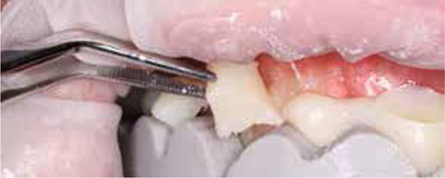

Bij het extraoraal onderzoek zie ik een lichte hypertrofie van de m. masseter. Intraoraal tref ik een ernstig versleten dentitie aan waarbij de slijtage niet passend bij de leeftijd kan worden genoemd (afbeelding 2-7 en tabel 1) .

Afb. 5

Lateraal aanzicht rechts.